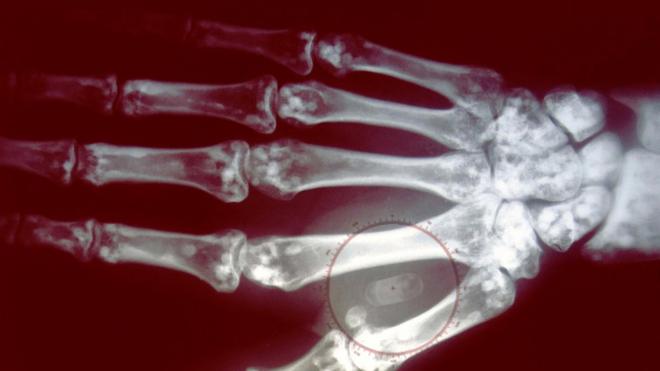

Betty Jo queria ter absoluta certezaregras da aposta esportivaque seu pai não era o homem que a criou, então, deu um passo além. Embora ele tivesse morrido três anos antes, ela tinha um pouco do cabelo dele e enviou a amostra para um laboratório para fazer um testeregras da aposta esportivapaternidade. O resultado da análise mostrou que eles compartilhavam 0%regras da aposta esportivaDNA.